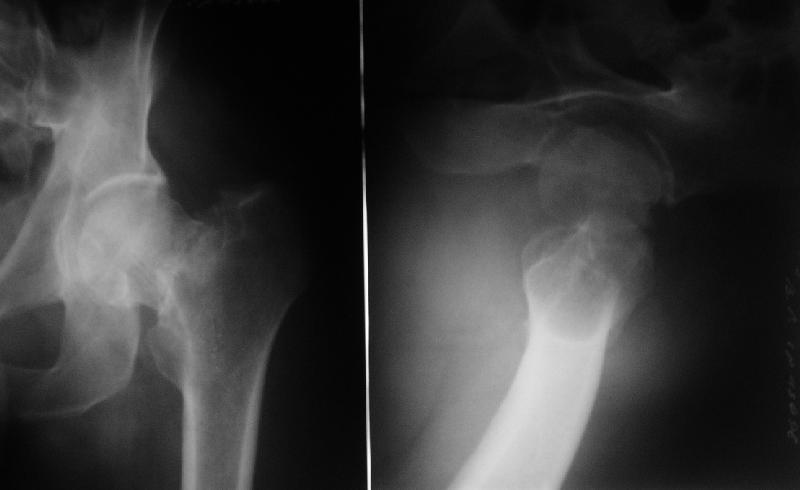

[Ortho] Нелеченный перелом шейки бедра

Поступил пациент 50 лет, из области. Травма 18.08.08. Лечили

консервативно. Сейчас вот чего-то спохватились и направили. Движения в

тазобедренном суставе практически безболезненны, кроме форсированной

внутренней ротации. В остальном проблем со здоровьем нет.

Рентгенограмма в приложении. Видимо, выбирать приходится в первую

очередь между вальгизирующей остеотомией и эндопротезированием.

Что в этой ситуации лучше предпринять? Есть ли еще какие-то варианты?